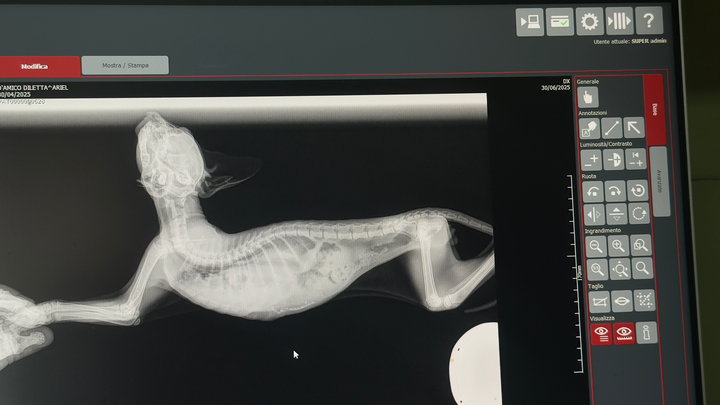

He was breathing slowly and with difficulty… so we took him to the vet. Sadly, we were told he had suffered a severe trauma: in simple terms, his stomach had moved into his chest cavity, putting pressure on his lungs.